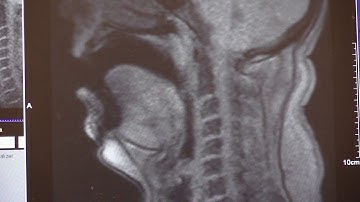

Final alignment result of real-time MRI video and EMA sensors